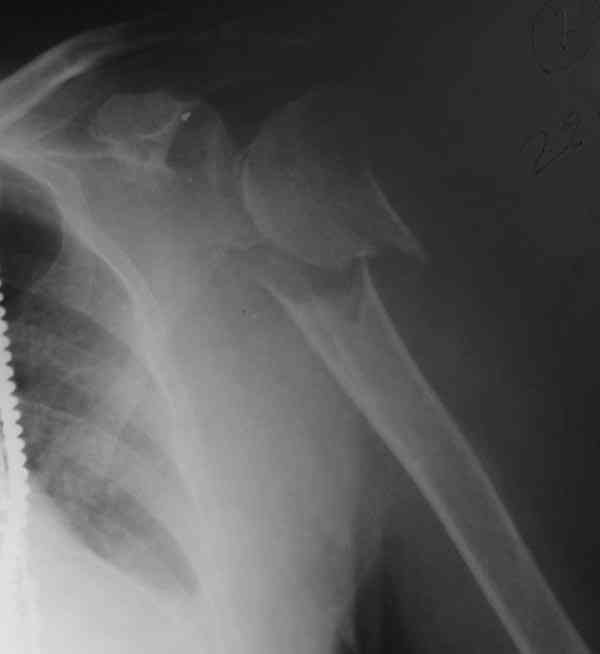

The fracture is completely displaced in the axial view. It is probably possible to align it with the patient in the vertical position, i.e. sitting or standing. However, I would use a locking plate for the tremendous pain relief it offers.

I am attaching the radiographs of the mother of a doctor. She has chronic renal failure for >10 years, diabetes mellitus and coronary artery disease. Age 62. She was offered the options of non-surgical management in a sling and surgery with a locking plate. She was given Tramadol for pain relief. Five days after injury, patient requested surgery, because of pain, inability to move without pain.